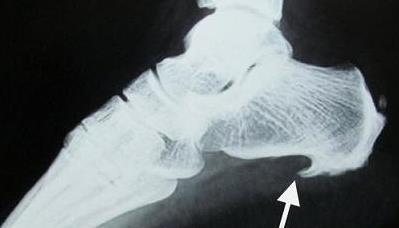

足跟骨刺图片

跟骨骨刺